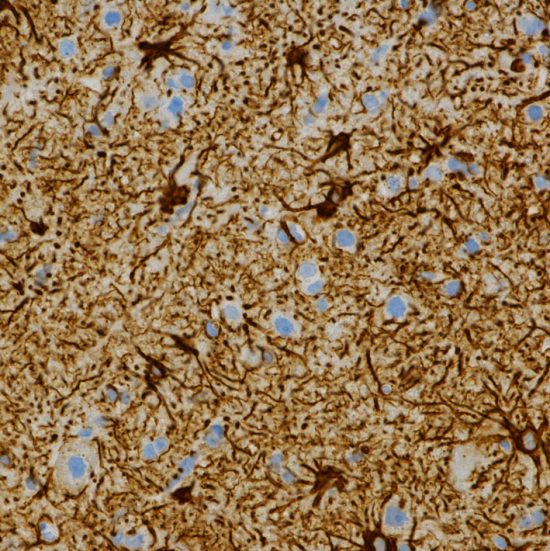

星細胞腫をGFAP染色したものです。星細胞は脳の神経細胞を支える役割をします。周囲に突起を伸ばした腫瘍細胞(濃い茶色)が,光のを放つキラキラ星のように見えます。